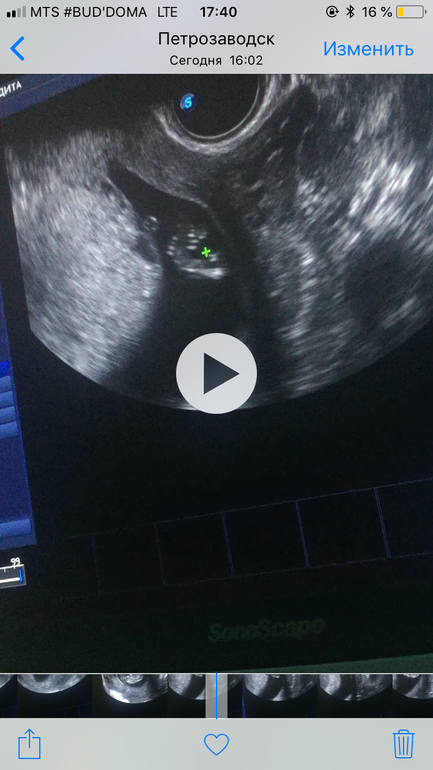

И все хорошо! Придраться не к чему. Почему это пред скриннинг, ктр маловат 43 мм. Но соответствует моему сроку. Абсолютно все хорошо, здоровый малыш, точнее малышка)))

ДАААА МЕЧТЫ СБЫВАЮТСЯ, на 95% сказали что девочка. Записала видео, смотрела как сидит ножка на ножку, вертелась и тёрла глазки.

И показала не то что параллельный бугорок, хотя на видео ничего не торчит, а показала формирующийся пирожок, фото прикреплю. Где крестик там этот «пирожок»